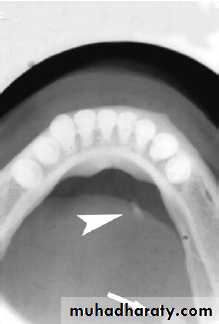

Stafne bone cyst

- most common ectopic salivary tissue .

Asymptomatic

clearly demarcated radiolucency of the angle of the mandible.

below the inferior dental neurovascular bundle.

No treatment is required.